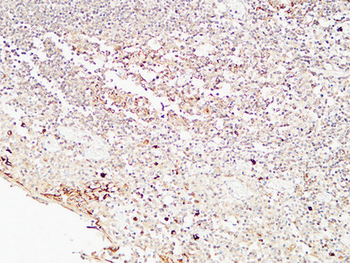

IHC staining of FFPE human lymph node with CD72 antibody (clone BU40). HIER: boil tissue sections in pH9 10mM Tris with 1mM EDTA for 20 min and allow to cool before testing.

IHC staining of FFPE human lymph node with CD72 antibody (clone BU40). HIER: boil tissue sections in pH9 10mM Tris with 1mM EDTA for 20 min and allow to cool before testing.